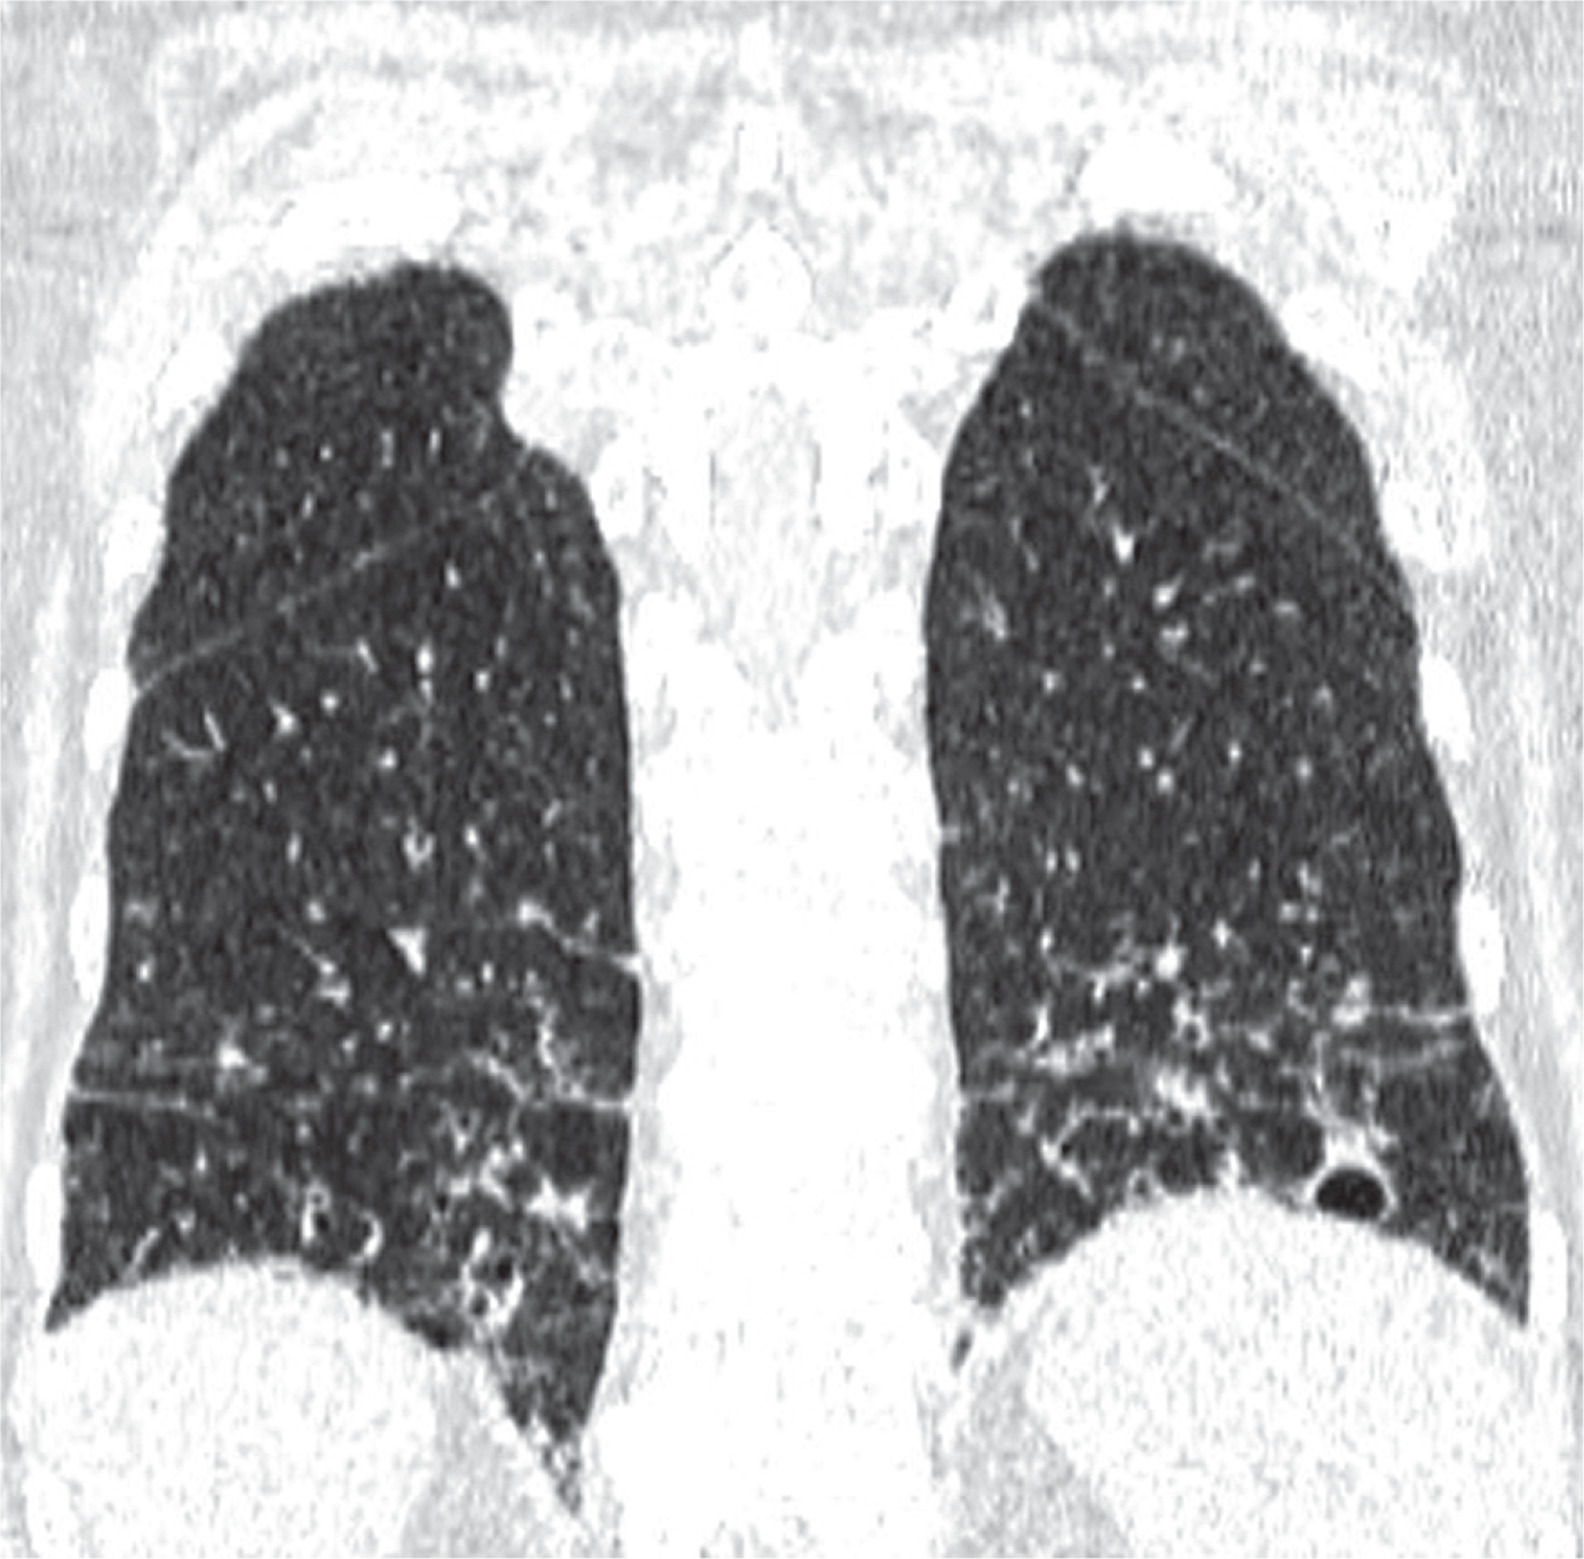

Figure 2

Baseline chest computed tomography, lung window: A) axial plane, B) coronal reconstruction. It shows multiple well-circumscribed, thin-walled, and variable sized lung cysts with round, oval, and irregular shapes with predominantly basal distribution. The largest cyst is located in the left lower lobe